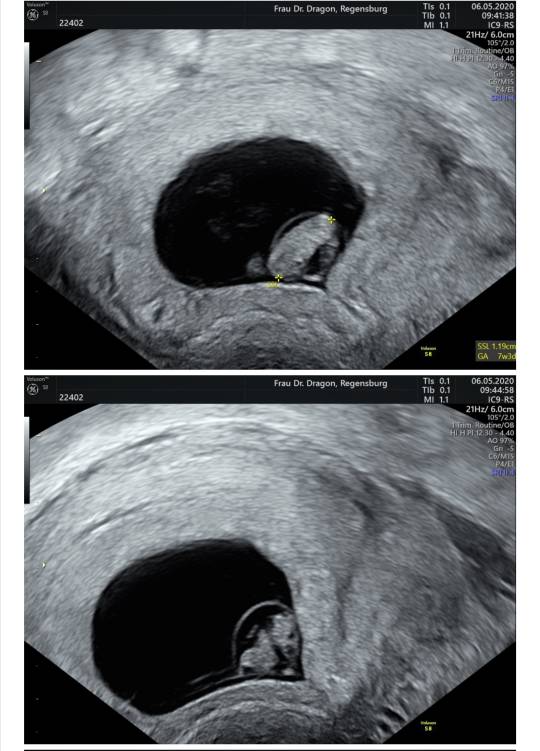

Jest serducho [emoji3590] waliło jak oszalałe - mały człowiek we mnie mieszka [emoji7]

Słabo go trochę widać na zdjęciu przez moją tkankę tłuszczową hehe... trudno, najwyżej nie bedzie miec ladnych zdjęć w brzuchu póki co [emoji13]

Termin z USG na 31.12 - 01.01. [emoji3059] Będzie impreza [emoji4]

Za nic nie pamiętam ile ma długości...8,4 mm? Już nie słuchałam taka byłam zakręcona.